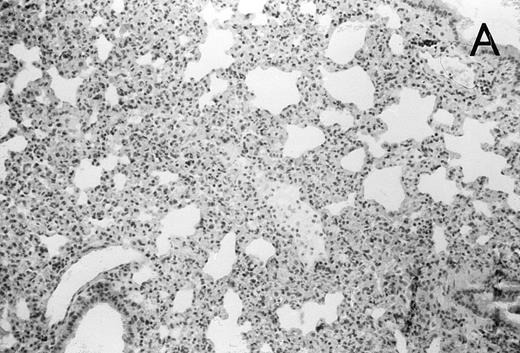

Histology further supported this observation. Control animals showed well-developed pneumonia with abscess formation (Fig3A) in their lungs, but in their livers, only small areas of inflammation with scattered microabscesses and foci of hepatic necrosis were observed (Fig 3B). In contrast, mice pretreated with G-CSF had only mild peribronchitic alterations in their lungs without signs of containment of inflammation such as abscess formation (Fig 4A). Livers and spleens of mice pretreated with G-CSF were severely altered, showing large abscesses which contained massive amounts of bacteria (Fig 4B). In addition, large necrotic areas surrounded by granulocytes were observed in the livers (Fig 4C). When MoAb III/5-1 was administered in addition to pretreatment with G-CSF, almost all changes observed in animals pretreated with G-CSF were reversed: there were only minor bronchial and peribronchial infiltrations by granulocytes (minimal change focal pneumonia), and the livers showed small microabscesses as observed in control mice. When treatment with G-CSF was started at 24 hours after bacterial challenge, a mixed pattern was observed. In the lungs, there was a beginning pneumonic reaction and a moderate perivascular and septal edema. However, in the liver there was almost no difference to the severe alterations observed in mice pretreated with G-CSF: huge abscesses loaded with bacteria joined extended necrotic areas.

(A) Micrograph of lung tissue 48 hours after intranasal infection with 1 × 103 CFU of K pneumoniae B5055 and pretreatment with G-CSF (50 μg/kg sc) at −48 hours, −36 hours, −24 hours, and −12 hours before infection. Peribronchiolar neutrophils without destruction of lung parenchyma. H&E; original magnification ×150. (B) Splenic abscesses in the red pulp containing numerous gram-negative bacilli are found. H&E; original magnification ×370. (C) Confluent hepatic necroses. H&E; original magnification ×150.